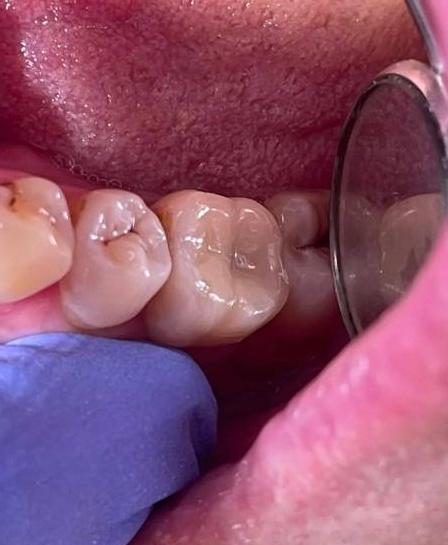

Непростой выбор

Здесь, казалось бы, обычная ситуация: старый моляр, старая пломба, тёмные края по периферии. Коричневый ободок, который пациент иногда списывает на налёт или «просто время пришло». Но за этим коричневым ободком пряталась история посерьёзнее.

Когда я убрал старую пломбу, открылось дно, которое могло испугать кого угодно. Кариозный дентин, размягчённый, тёмный, подбирался почти к самой пульпе. То есть к нерву, к сердцу зуба. Ещё пара месяцев, ещё одна жевательная нагрузка — и начался бы пульпит. А там либо боль, либо каналы, либо прощай, нерв.

И передо мной встал выбор: классический путь «перестрахуюсь и убью нерв» или путь «попробую сохранить».

Я выбрал сохранять.

Потому что живой нерв — это живой зуб. Это термометрия, это трофика, это сигнальная система, которая работает. Мёртвый зуб — уже просто конструкция. А здесь был шанс оставить зуб живым.

Я работал с увеличением, чтобы видеть каждый миллиметр дна. Убирал поражённые ткани максимально аккуратно, не вскрывая пульпу. Где-то оставил защитный слой, где-то обработал антисептиками, которые не агрессивны к нерву.

Потом — лечебная прокладка, которая стимулирует выработку вторичного дентина. Та самая «броня», которую зуб нарастит сам, если ему помочь.

Дальше — восстановление анатомии. Материал, форма, контакты, фиссуры. Чтобы зуб не просто «был», а работал, жевал, жил в прикусе.

На фото «После» — моляр, у которого нерв остался живым. Он не болит, не реагирует на холод, не напоминает о себе. Он просто жуёт, как и положено здоровому зубу. И при этом он свой, родной, с живым сердцем внутри.

Этот случай про врачебную сдержанность. Про то, что не всегда нужно идти по пути максимального удаления. Иногда достаточно остановиться на миллиметр раньше, чтобы сохранить то, что дала природа. И зуб скажет спасибо долгой и здоровой жизнью: